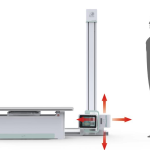

| Size | 2120*965*450-740mm |